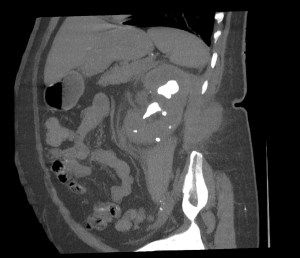

CASO 2: Paciente de 68 años con dolor en flanco izquierdo, fiebre y malestar general. A la exploración existe enrojecimiento de la piel con sensación de masa palpable y puño percusión muy positiva.

El paciente es alégrico al Iodo. Se realiza TC sin contraste para ampliar estudio.

Todos estos hallazgos están en relación con una Pielonefritis Xantunogranulomatosa que afecta al riñón derecho junto con una colección que ha fistulizado a región lumbar.

- Pielonefritis Xantunogranulomatosa.

- Es una forma infrecuente de pielonefritis crónica, de origen obstructivo, caracterizada por la formación de un absceso granulomatoso que puede extenderse al EPR-, severa destrucción renal y un cuadro clínico de fiebre, malestar general, dolor en el flanco y masa renal, a veces palpable.

- Los hallazgos en TC pueden ser:

- Uni o bilateralidad de la lesión.

- Afección difusa o localizado.

- Litiasis de tipo coraliforme, calcificaciones intraparenquimatosas.

- Aumento difuso del tamaño renal.

- Áreas hipodensas o hipoecogénicas dentro de la lesión renal debidas a cálices dilatados, abscesos o áreas de necrosis parenquimatosa.

- Pobre o nula eliminación del medio de contraste en el riñón afectado.

- Compromiso inflamatorio que excede los límites del riñón y genera colecciones periféricas o extensión hacia vísceras vecinas.